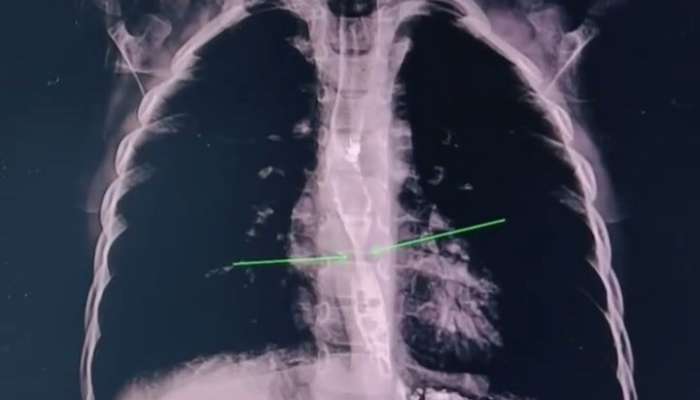

Həkimlər